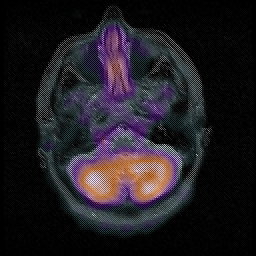

Huntington's Chorea, MR -- Slice #2